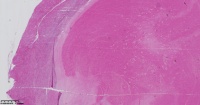

平滑肌瘤伴梗死?

性别

女

年龄

37岁

临床诊断

剖宫产术后,子宫肌瘤

一般病史

标本名称

子宫肌瘤

大体所见

子宫平滑肌瘤伴红色样变